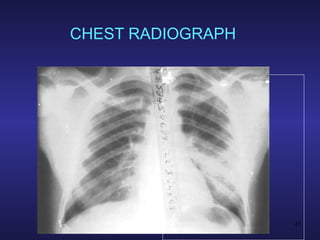

CLINICAL FEATURES PULMONARY Common association with ARDS Lung edema resulting from increased alveolar-capillary permeability Dyspnea & hypoxemia Noncompliant “heavy” lungs Bilateral pulmonary infiltrates Abnormal opacities on CXR

CHEST RADIOGRAPH